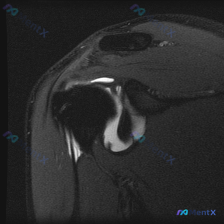

看到这张肩关节MRI,大家一起看看思路对不对,整理出来分享给大家: 病例影像基础信息 这是一张肩关节MRI冠状位T2加权图像,问题核心是观察影像中的软组织液体异常,我们从全影像结构一步步梳理: 核心影像表现整理 1. 骨骼关节结构:肱骨头形态和骨髓信号无明显异常;关节盂形态尚可,上盂唇可见条带状高信...

整理了一个肩部MRI的病例讨论材料,报告里的核心发现有几个: - 冈上肌肌腱在肱骨大结节附着处有低信号连续性中断,提示全层撕裂,断端有回缩和液体填充 - 肱骨大结节附着点下方有片状高信号,考虑骨髓水肿或炎症反应 - 关节腔内(腋囊)有大量液体高信号,肩峰下-三角肌下滑囊也有积液 原问题是问盂唇病理,...

最近看到一个肩部MRI病例,患者主要表现为肩痛。目前只有单层冠状位T2加权图像,先放出来大家讨论一下: 影像学发现 - 肱骨大结节止点处冈上肌腱深层(关节面侧)连续性中断,可见局灶性高信号,与关节腔积液相通 - 冈上肌腱轮廓尚可,未见严重萎缩或脂肪浸润 - 肩峰下-三角肌下滑囊内有高信号积液 - 盂...